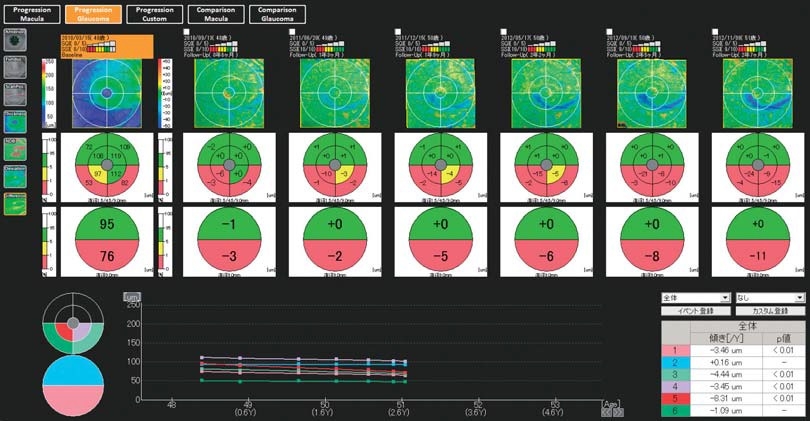

複数データの経過観察